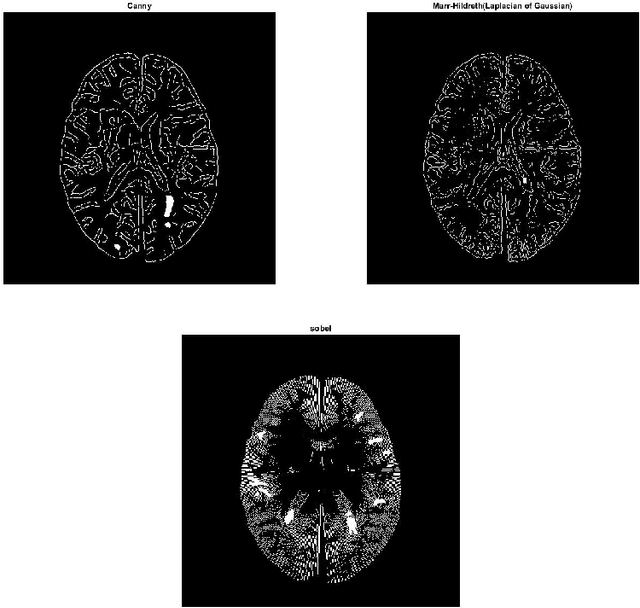

Abstract:Magnetic resonance images (MRI) play an important role in supporting and substituting clinical information in the diagnosis of multiple sclerosis (MS) disease by presenting lesion in brain MR images. In this paper, an algorithm for MS lesion segmentation from Brain MR Images has been presented. We revisit the modification of properties of fuzzy -c means algorithms and the canny edge detection. By changing and reformed fuzzy c-means clustering algorithms, and applying canny contraction principle, a relationship between MS lesions and edge detection is established. For the special case of FCM, we derive a sufficient condition and clustering parameters, allowing identification of them as (local) minima of the objective function.